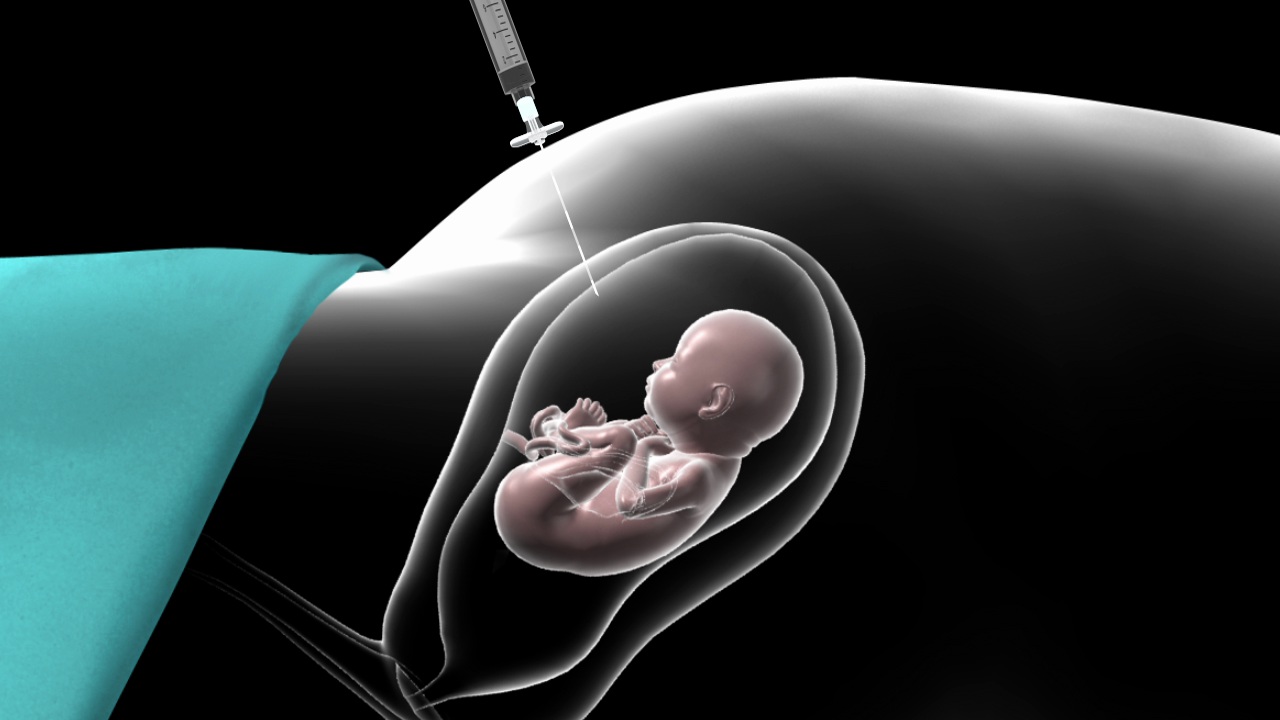

Amniocentesis

Amniocentesis is a prenatal diagnostic procedure used to assess the health and development of a fetus during pregnancy. It involves removing a small amount of amniotic fluid